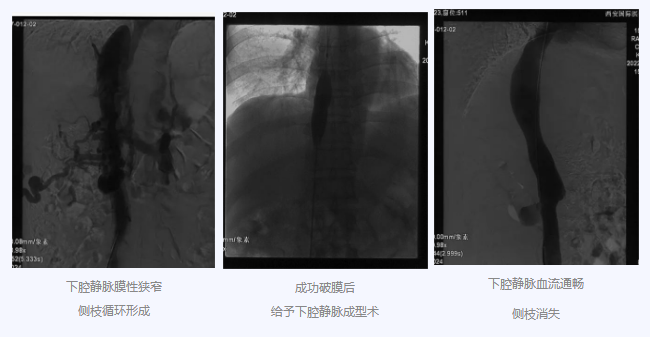

入院后,在韓國宏院長(zhǎng)的安排下,臨床經(jīng)驗(yàn)豐富的醫(yī)師給老謝做了B超、CT 等檢查,結(jié)果顯示:三支肝靜脈近心端閉塞,肝內(nèi)側(cè)枝循環(huán)形成,下腔靜脈近心房入口處隔膜樣狹窄,隨后的DSA血管造影也證實(shí):下腔靜脈狹窄,且有側(cè)枝形成,最終確診困擾老謝20年的疾病為混合型布加綜合征,是一種罕見病。

明確診斷后,韓院長(zhǎng)帶領(lǐng)團(tuán)隊(duì)縝密分析老謝的病情,為其制定最佳的治療方案,考慮到老謝的根本病因是下腔靜脈阻塞,介入手術(shù)成為首選治療方法,通過微創(chuàng)介入手術(shù),可準(zhǔn)確打通患者的閉塞血管,癥狀迅速緩解。做好充分術(shù)前準(zhǔn)備后,為患者行“下腔靜脈成型術(shù)”,精準(zhǔn)定位快速貫通,閉塞的下腔靜脈順利開通,手術(shù)圓滿完成。